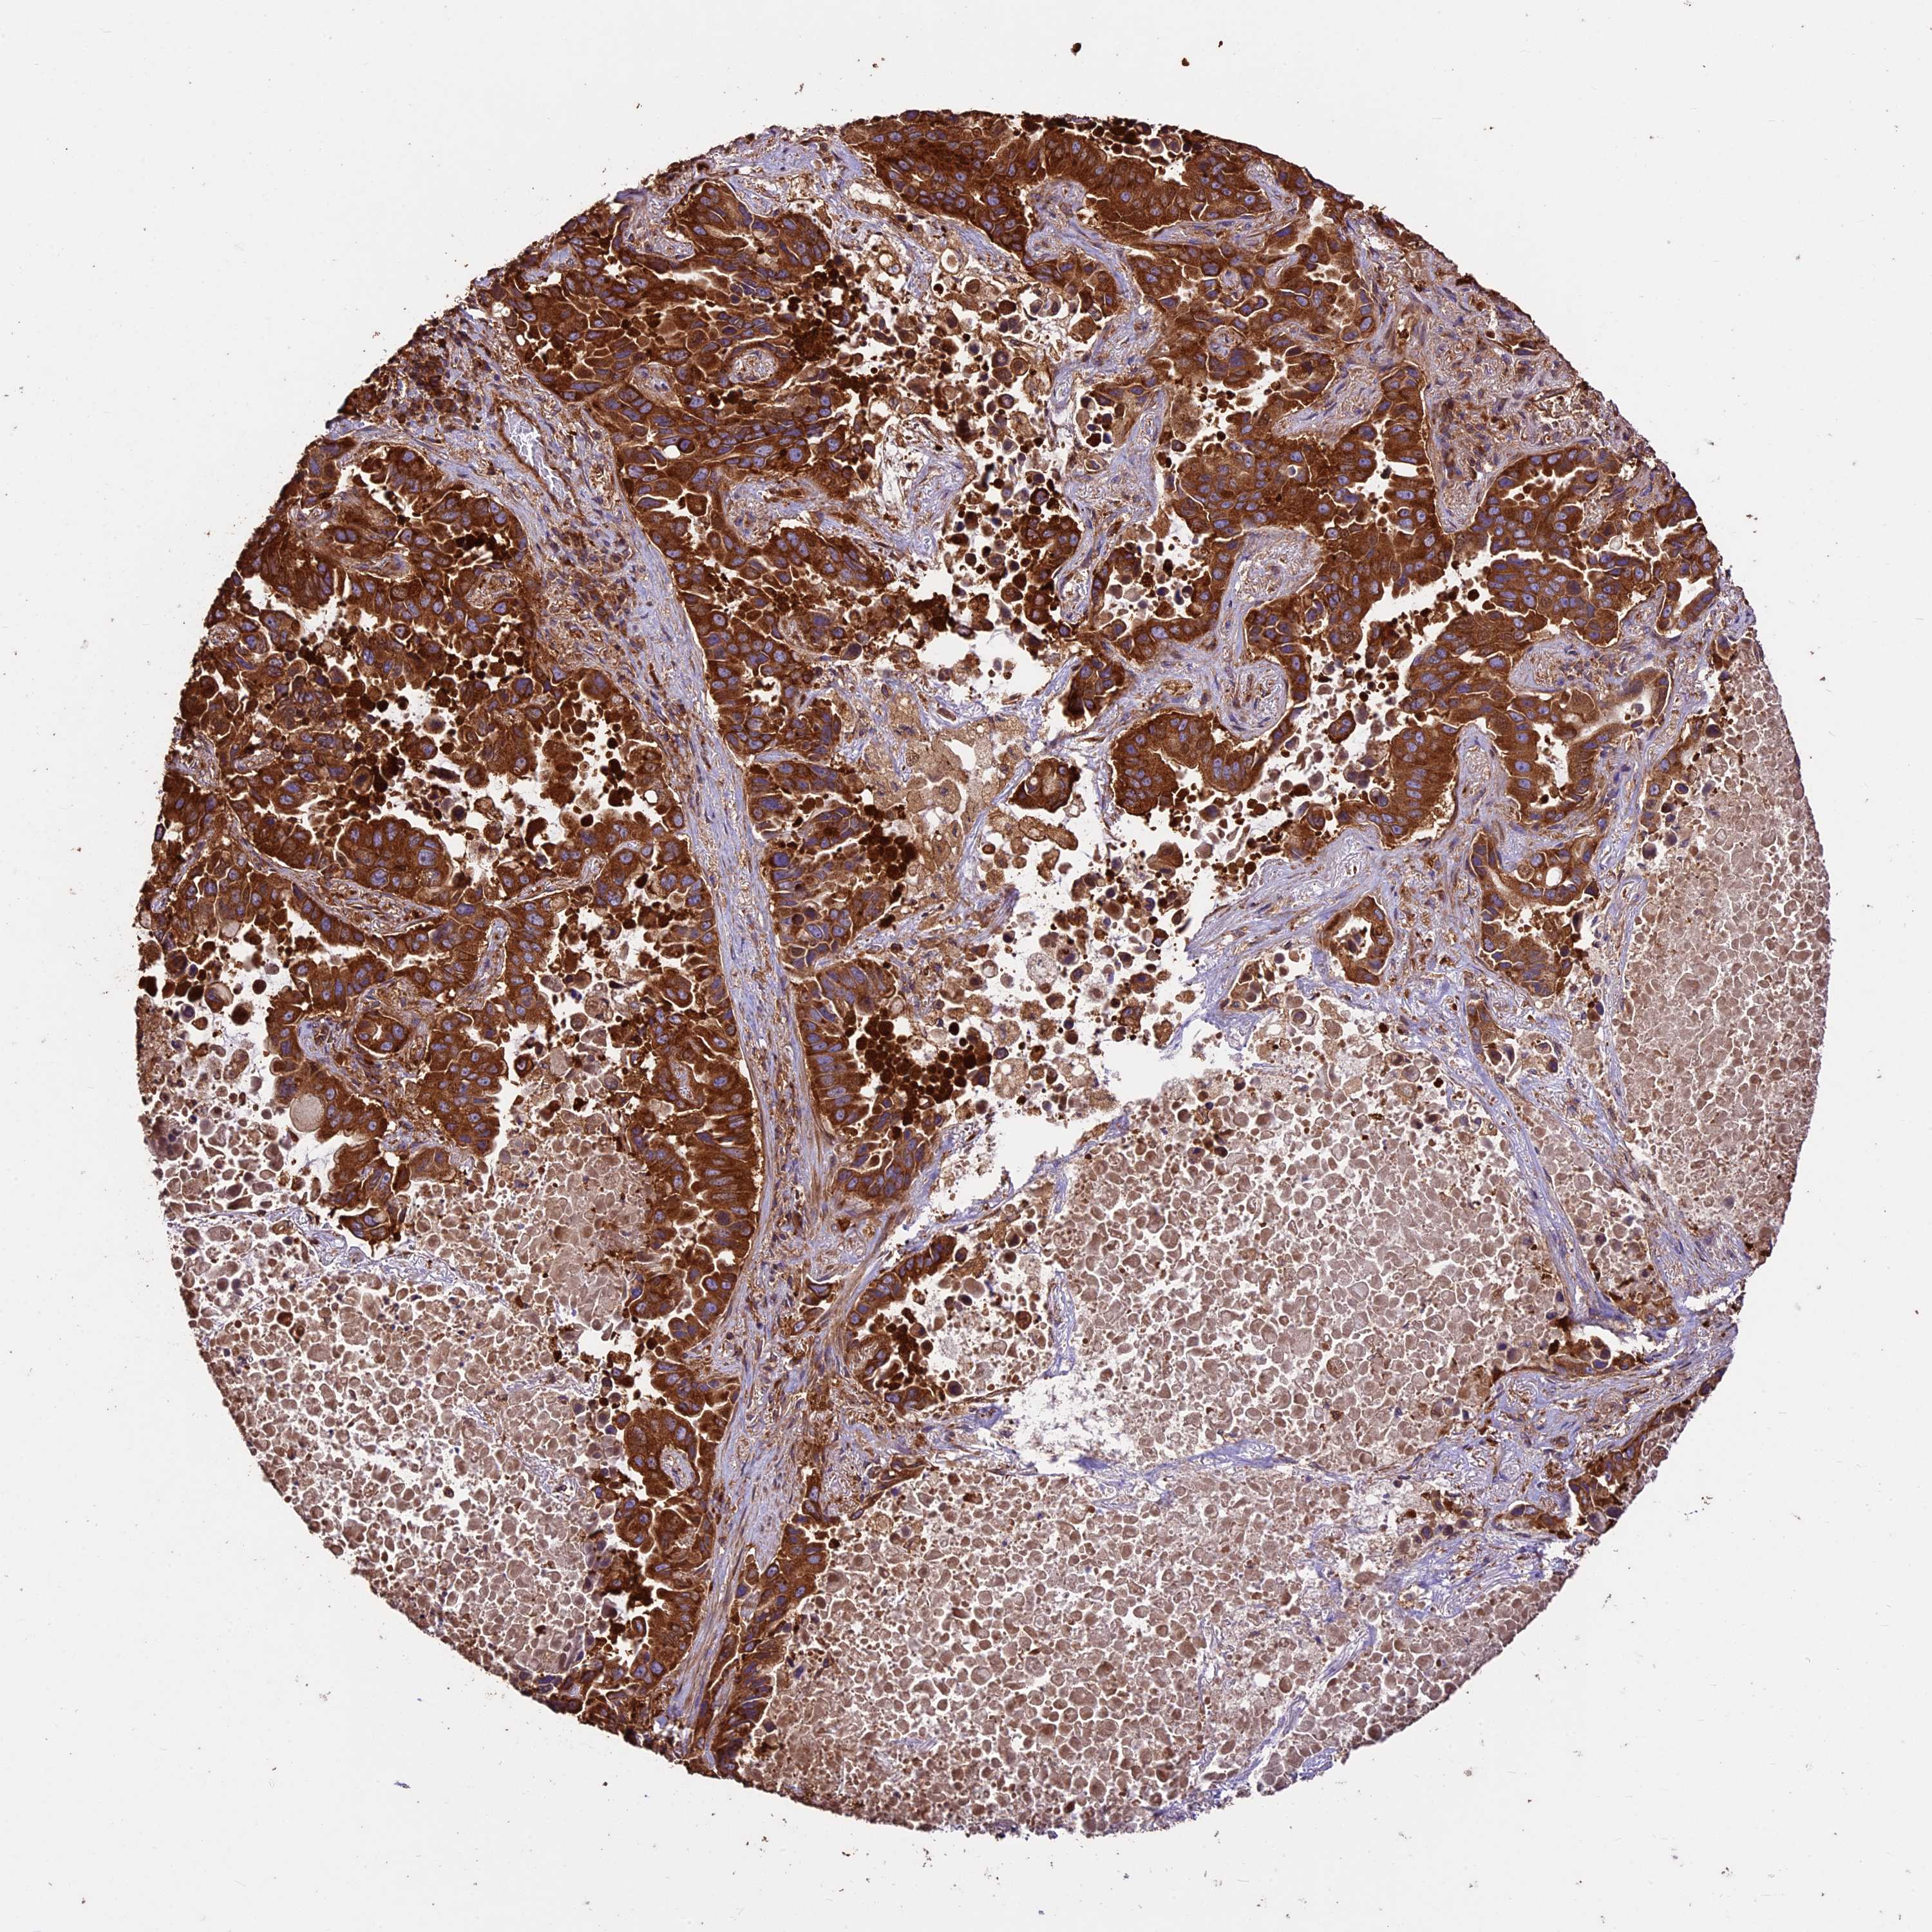

KARS1